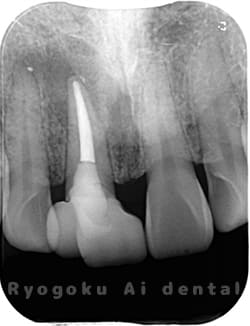

Case02

-

- 原因

- 慢性根尖性歯周炎

- 治療期間

- 1回(消毒・洗浄も含めると3回)

- 治療内容

- 歯根端切除術

- 治療費用

- ¥110,000

他院で抜歯と判断され、インプラント治療を提案された患者様です。被せ物を外さずに、歯の根尖部に外科的にアプローチし、病気の部分を除去しました。

<リスク・副作用>

外科手術のため、術後に出血、痛みや腫れ、違和感を伴います。口腔内の状態によっては適応できないことがあります。歯根端切除で治らなければ抜歯を検討しなくていけない場合もあります。